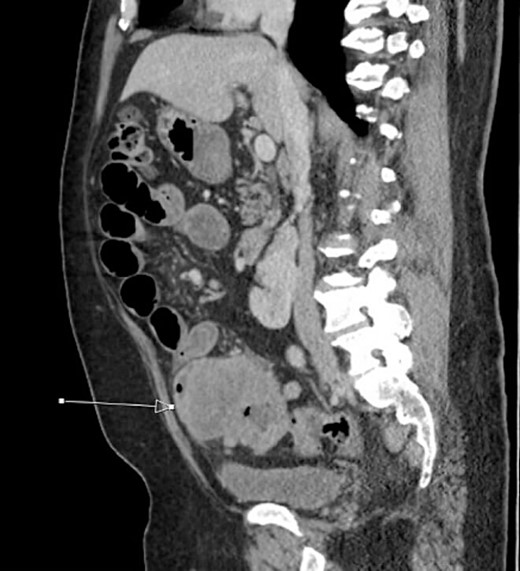

Initial CT imaging, sagittal cut, showing necrotic mass causing small bowel obstruction.

The patient was initially managed nonoperatively with conservative measures including nasogastric (NG) tube decompression, pain control, and serial abdominal exams. Surgery was consulted once CT imaging was obtained (Figs 1–3) and recommended that the patient undergo surgery to resect the identified mass and relieve the obstruction. During the surgical exploration, a mass originating from the terminal ilium was identified that was densely adhered to the peritoneum, bladder, and sigmoid colon, requiring careful dissection. The mass, three lymph nodes, and 29 cm of associated small bowel segment was resected with grossly negative margins, with the mass measuring 7 cm × 8 cm × 9.5 cm. A side-to-side anastomosis was created and the specimens were sent to pathology for further investigation. Postoperatively the patient was hospitalized for 7 days for pain control and monitoring. On postoperative day eight he was discharged with follow up appointments with oncology, general surgery, and a referral to an academic cancer center.